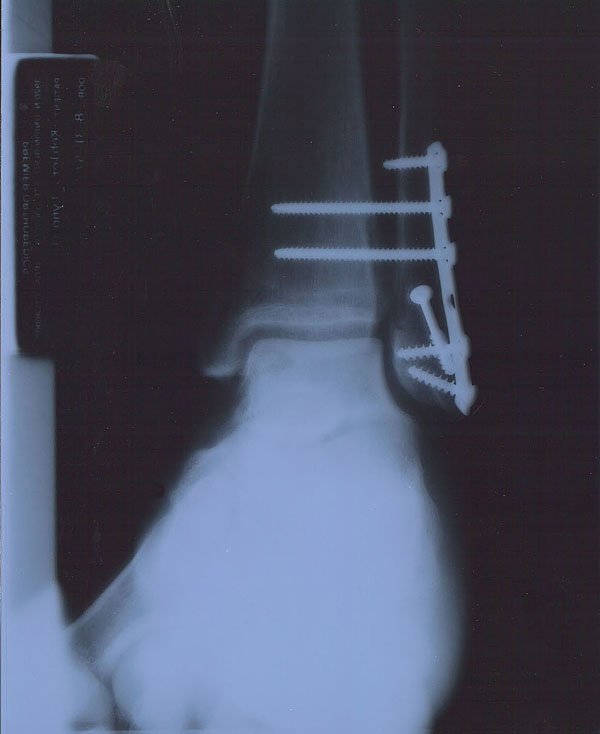

Dave told me to head over to to Memorial Hospital that afternoon. Bear in mind, this is the Wednesday before Thanksgiving! By the time the anesthesiologist started administering the “Milk of Amnesia,” it was between 5:30 and 6:00 p.m. Kudos to Dr. Walden for working me in and making it happen – I owe him one! Anyway, after a while I woke up with a nice anesthesia hangover and this lovely piece of work:

Yeah, that’s a plate and six screws, including two so-called “syndesmotic” screws that go through both the tibia and fibula to hold the ankle joint together during the healing process. Only my fibula was broken, down in the region where the three lower screws converge. Funny (yeah, hehe…), they look like a bunch of drywall screws. Just what I needed at 50!